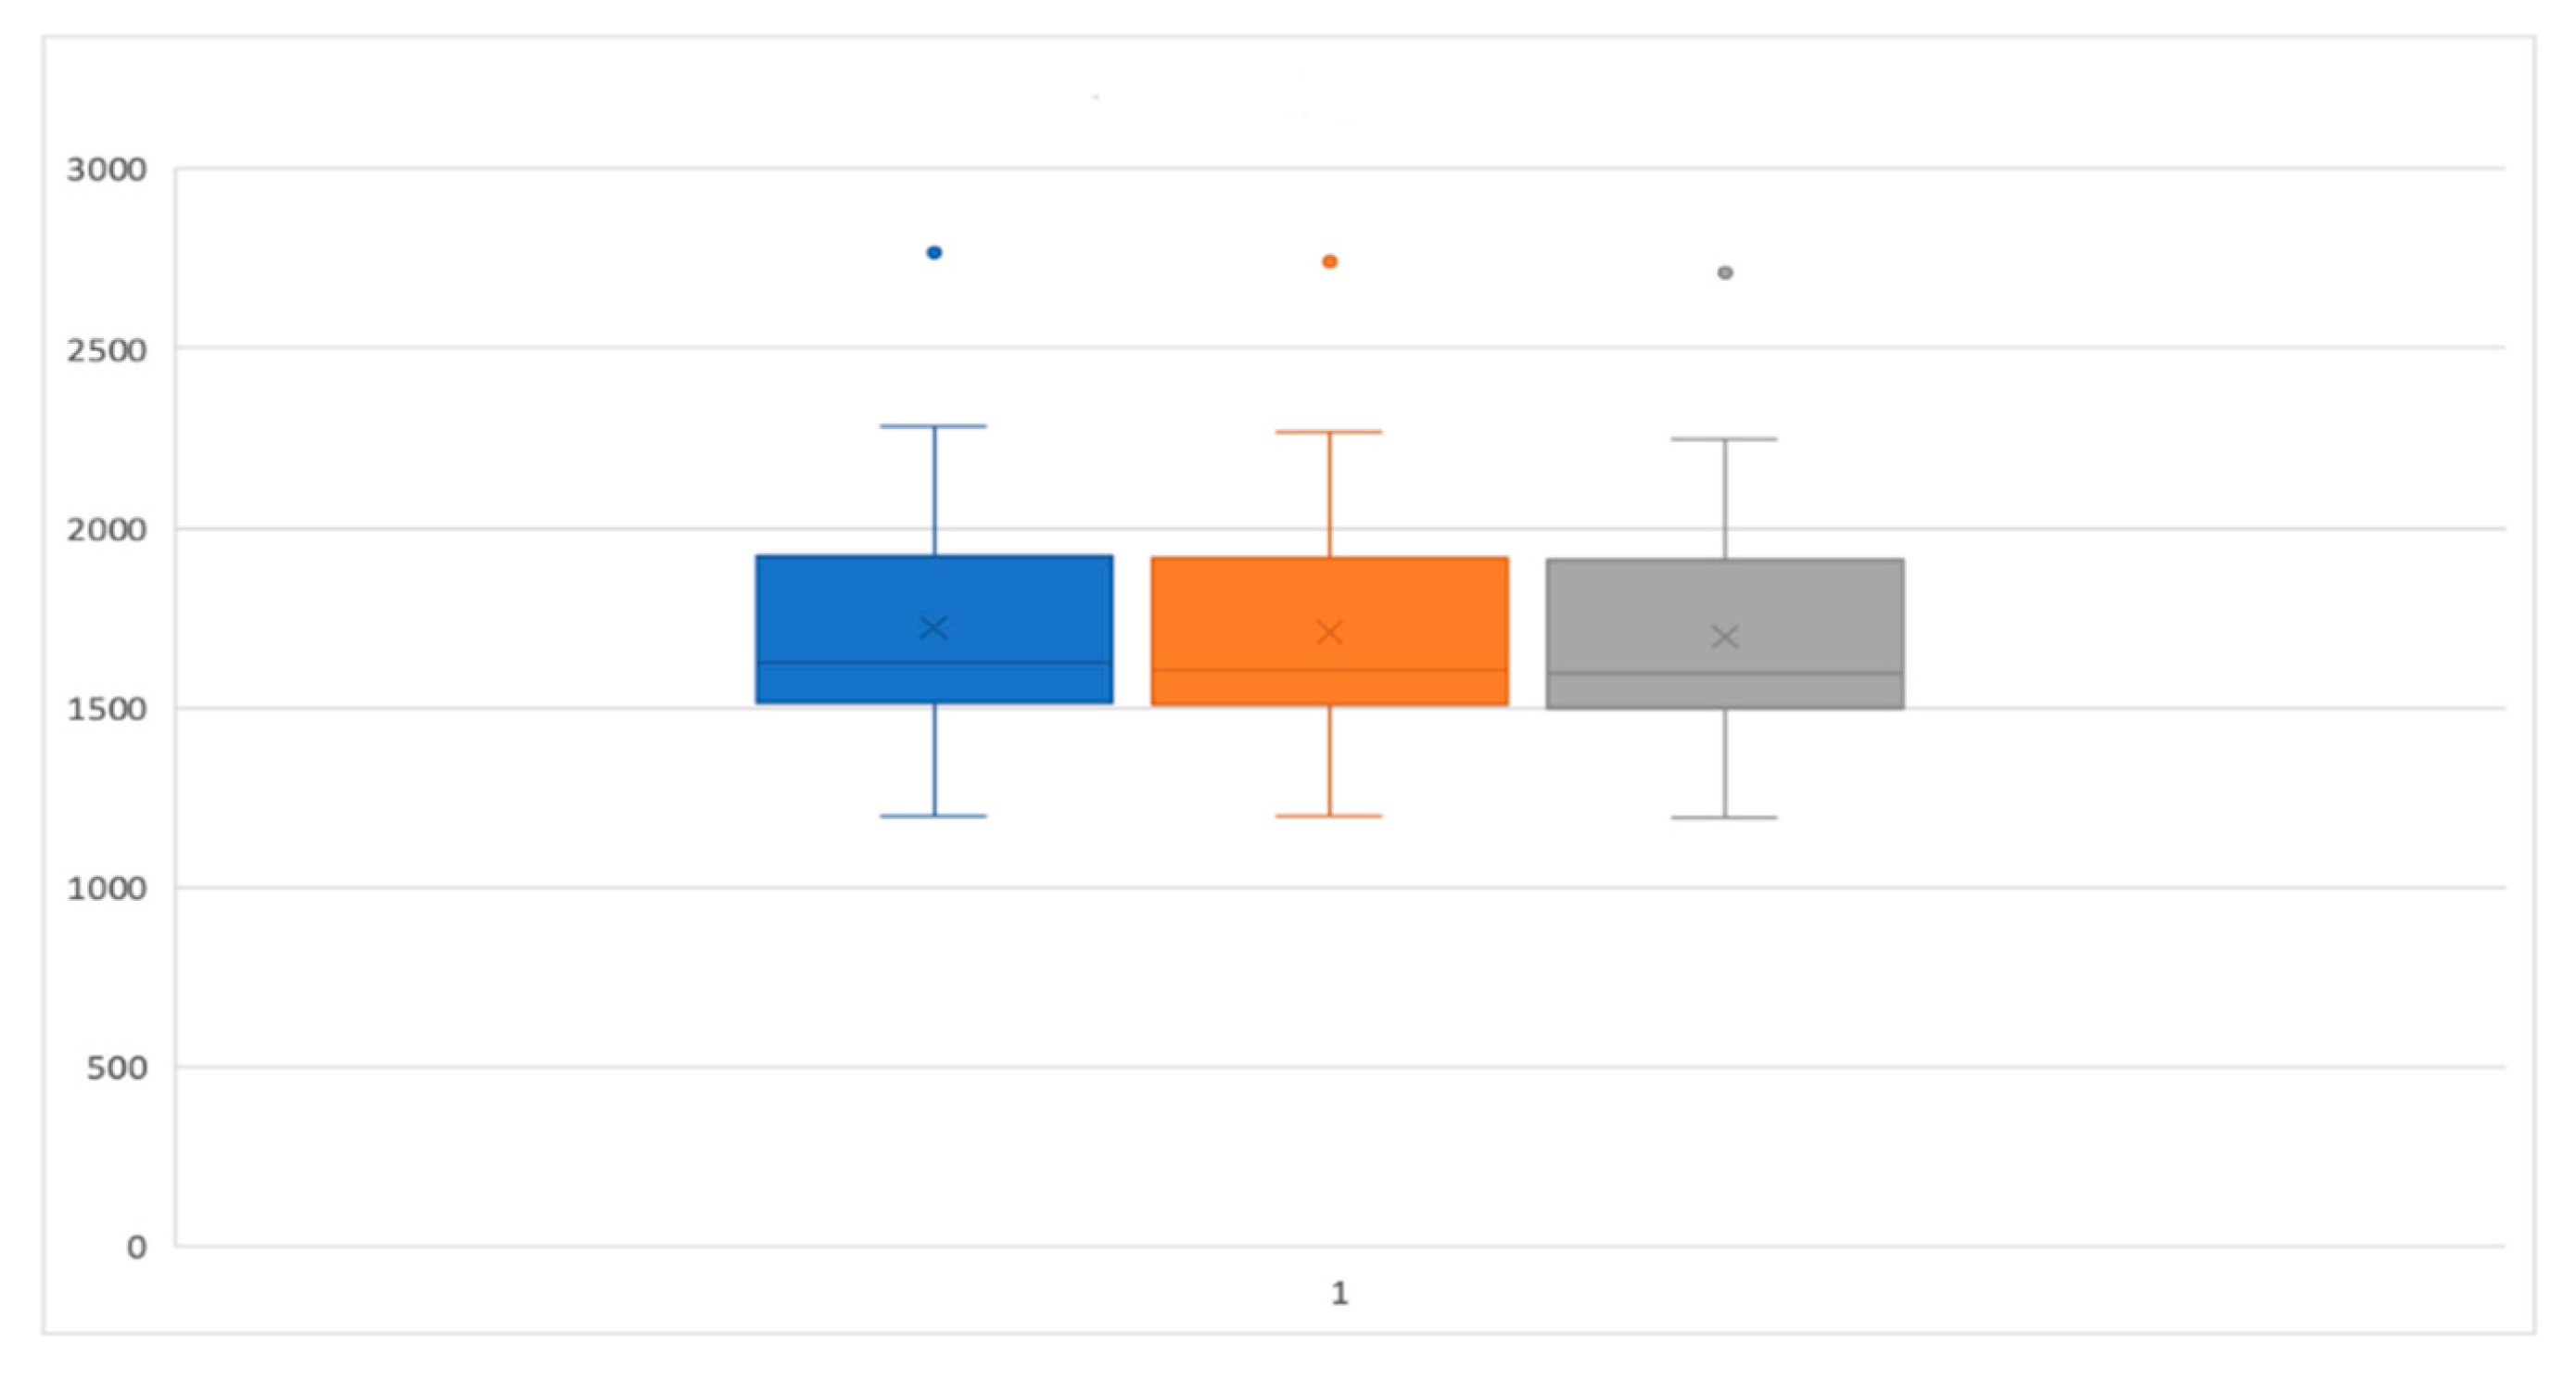

3. Results